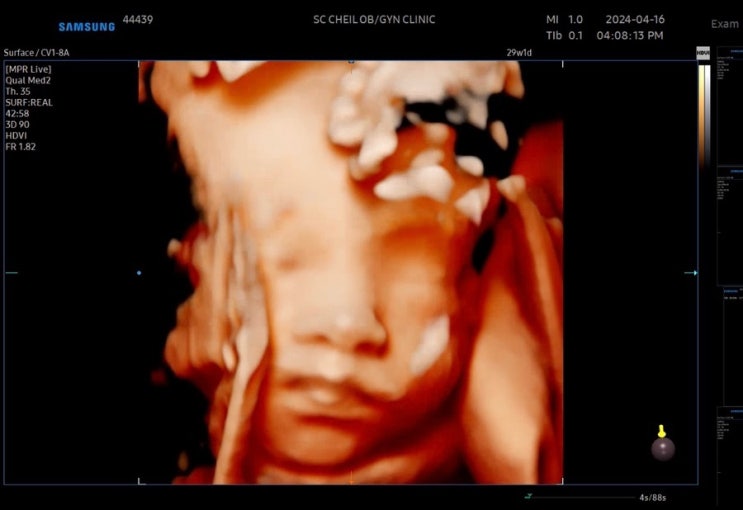

임신 후기 진입! 임신 28~29주 차 기록

벌써 임신 후기에 접어들었다. 몸무게 앞자리가 바뀌고 배도 엄청나게 많이 나왔다. 임신 28~29주 차 일상...